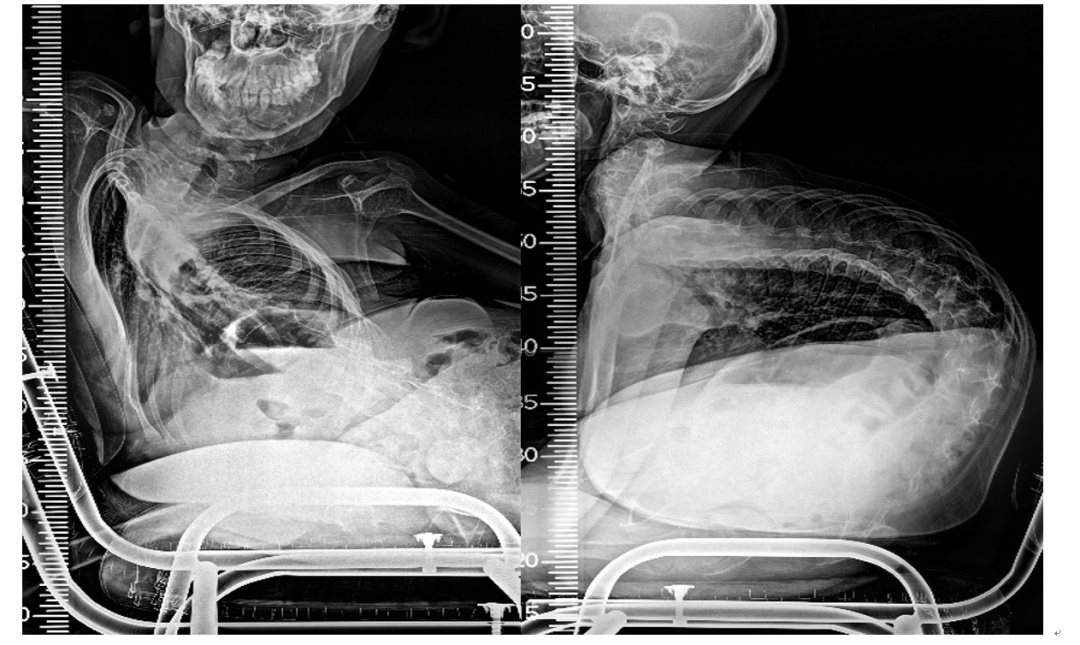

SMA导致的脊柱侧凸符合典型的神经肌源性脊柱侧凸的特点,呈长“C”型弯曲,约90%患者表现为单一弯曲,其中约80%为胸腰弯。除进展较快的脊柱侧凸外,脊柱后凸也常见于SMA患者,尤其是逐渐丧失独坐能力的II型患者脊柱后凸程度更加严重。

SMA合并脊柱侧弯影像(图)